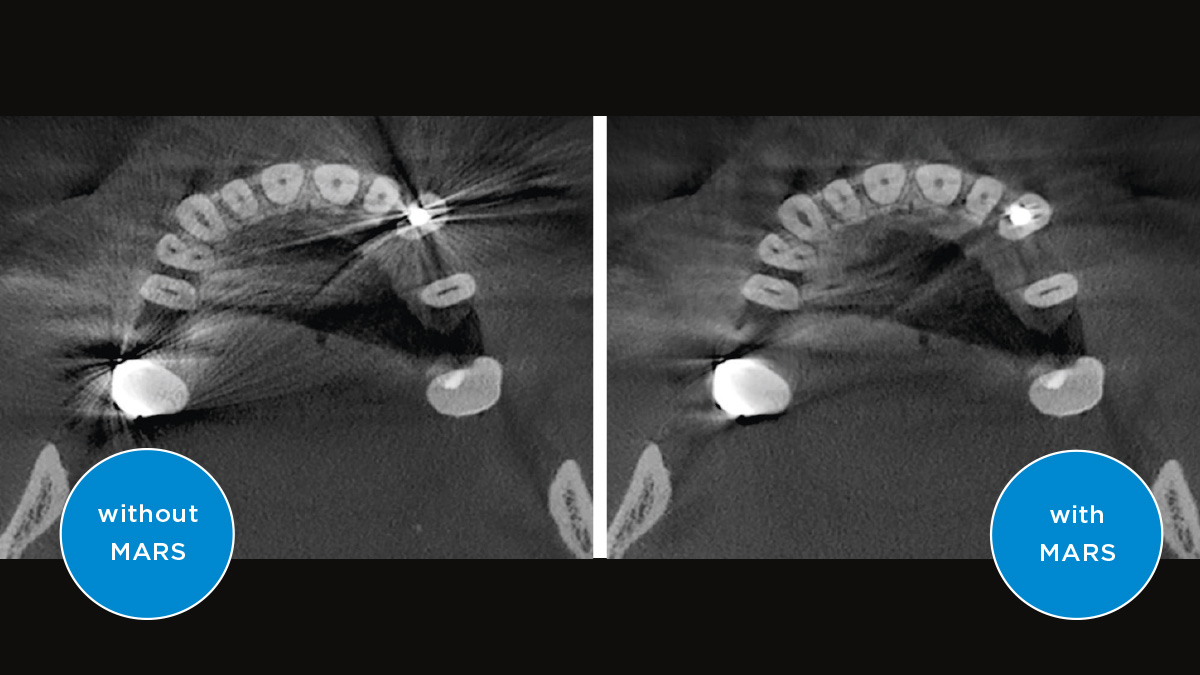

Właściwa ostrość jest kluczowa dla uzyskania doskonałych zdjęć panoramicznych. Dzięki funkcji autofokus automatycznie otrzymasz obraz z najlepszą możliwą ostrością. Tomografy i pantomografy od Dentsply Sirona działają na takiej zasadzie, że wykonują kilka tysięcy pojedynczych zdjęć w jednym cyklu i automatycznie identyfikują obszary, w których szczęka jest optymalnie ustalona. Bez dodatkowych czynności ręcznych obrazy te są następnie wyświetlane w postaci ostatecznego ostrego obrazu.

Tylko niektóre części obrazu są ostre, podczas gdy inne obszary są rozmyte.

System wykrywa odpowiednie obszary z kilku tysięcy pojedynczych obrazów w jednym cyklu i automatycznie identyfikuje obszary, w których szczęka jest optymalnie ustalona.

Ostre obrazy.